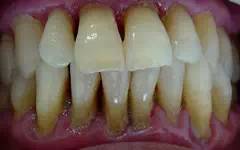

中期牙周炎:牙周袋進一步加深,牙齒松動、移位

晚期牙周炎:牙槽骨幾乎完全被破壞,牙齒松動、脫落